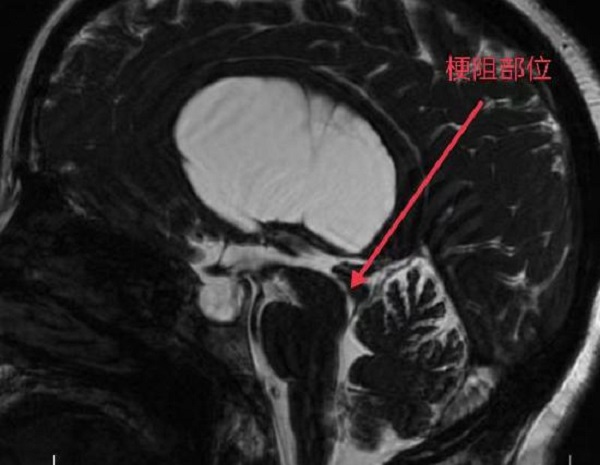

随着神经内镜设备的不断更新和微侵袭技术的快速发展,脑室镜下第三脑室底造瘘术(ETV)优势凸显, 已经成为了梗阻性脑积水的首选。近日,二一五医院神经重症监护室在成功开展脑积水之脑室镜下三脑室底造瘘术后,原有...